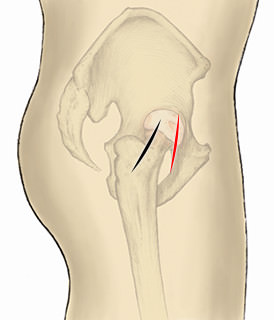

従来の手術法

前外側進入法(ALS)は黒で明示

前方進入法(DAA)は赤で明示